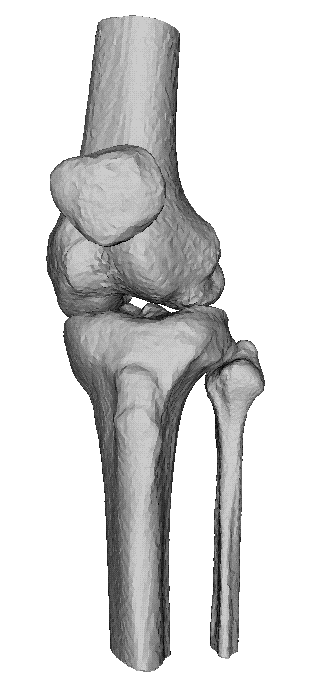

CT van het skelet

Een Ct-scan van het skelet wordt uitgevoerd wanneer er een verdere evaluatie nodig is van een letsel dat gezien is op een klassieke foto. Denk aan fracturen, luxaties e.d., maar ook aan metastasen, artrose,…Zo kan het bijvoorbeeld zijn dat een letsel niet duidelijk genoeg voorkomt op de foto’s en dat er dus twijfel bestaat. Maar ook kan het zijn dat een CT-scan noodzakelijk is om een duidelijk beeld te verkrijgen van een uitgebreide fractuur, om verdere behandeling te bepalen.

Dankzij de moderne computertechnieken is het niet alleen mogelijk om axiale beelden te maken. (lees schijfjes dwars op het lichaam) Maar ook om die beelden te reconstrueren tot een 3D-model. Dit geeft vaak een duidelijk beeld van het bot en zijn letsel.